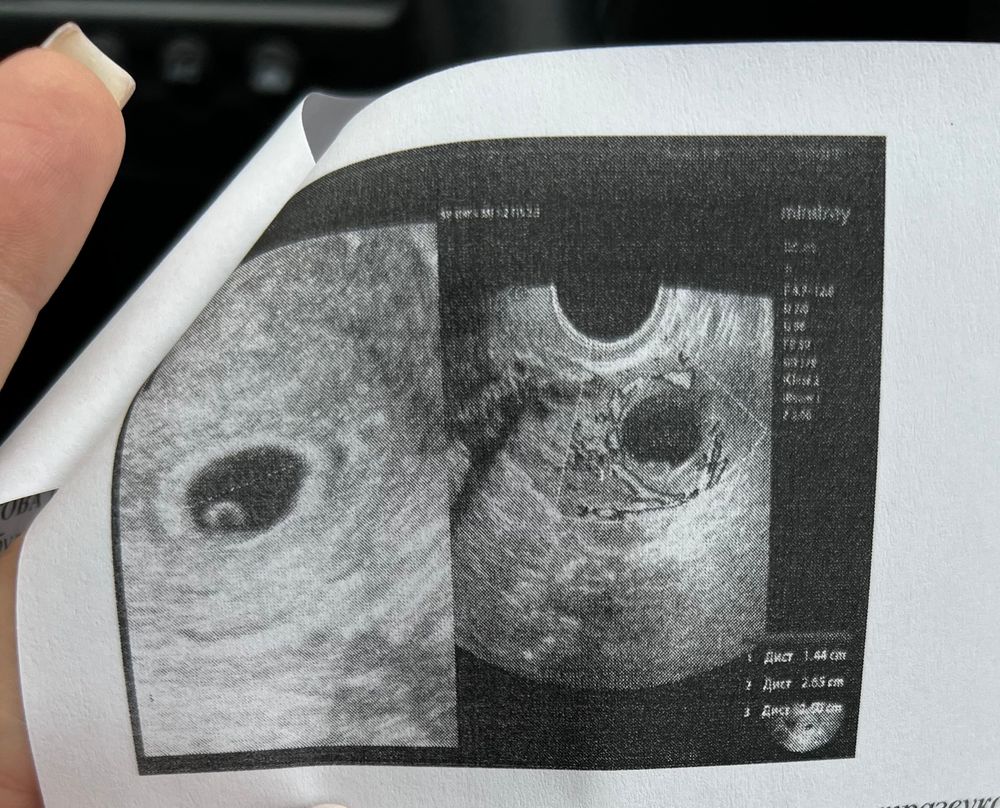

УЗИ на ранних сроках беременности: плодное яйцо 4 мм - это норма?

Делала узи первое 6 дней назад, плодное яйцо было 4 мм

У меня на 18дпо, это 3 дня задержки плодное яйцо было 4 мм. Думаю у вас примерно такой же срок был Когда обнаружили .в 6 недель 3 дня уже обнаружили эмбриона . Сейчас уже 26 недель беременности . Так что у вас все хорошо , не переживайте